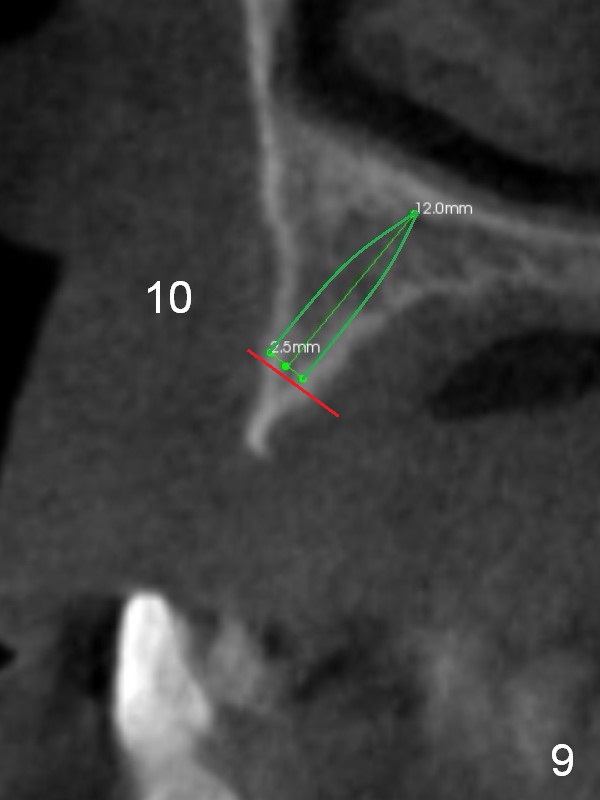

After implant reconstruction of the lower right and left (including #19) regions, the same treatment is considered in the atrophic anterior maxilla (#8-13) for anchorage for upper left molar cross bite correction. The smallest implants are to be placed in the each of the sites with different strategies. For example, at the site of #8 (Fig,1,2), ridge split with wheel (Fig.3) and microsteotomes (Fig.4) are used to place 1-piece implant (3x14 mm). The site of #9 has a pointed ridge and a wide base (Fig.6); a 1-piece angled implant (3x14 mm 15 °) is placed palatally (Fig.7). The ridge and base at #10 are narrow (Fig.8); after truncating the pointed ridge, a 2.0 or 2.5 mm 1-piece implant is placed parallel to the palatal wall (Fig.9).